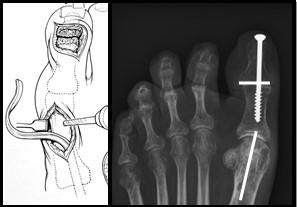

Calcaneus osteotomie

Bij een calcaneus osteotomie wordt het hielbot doorgezaagd en meer naar de buitenzijde verplaatst. De achtervoet komt zo meer van de “O” positie in een “X” positie.

Het vastzetten van beide botdelen gebeurt meestal met een schroef vanuit de hiel, middels een apart litteken.

Figuur 1: Voorbeeld van een calcaneus osteotomie. H=hielbot (calcaneus). De witte streep op het linker plaatje is de locatie van het litteken. De Rode pijl wijst naar de schroef. Op het meest rechtse plaatje zie je de verschuiving van het hielbot naar de buitenzijde